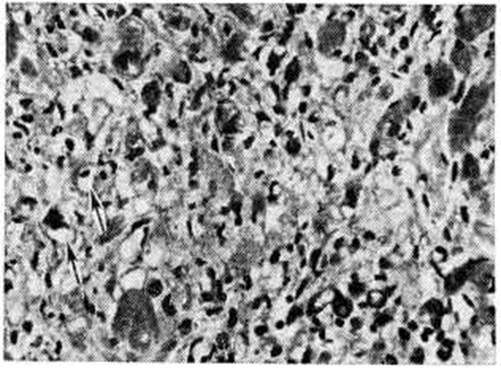

В заключительной стадии поражены обширные участки миокарда обоих желудочков, особенно — левого. В основном выявляются дистрофические и некротические изменения миокардиоцитов, начиная от вакуолизации перинуклеарной зоны цитоплазмы (смотри полный свод знаний Вакуолизация) и до цитолиза (рисунок 2) с полным растворением тел клеток (смотри полный свод знаний Цитолиз). От клеток остаются только следы в виде мелких зёрен липофусцина. В результате образуются ареактивные участки депаренхимизации миокарда (рисунок 3) с так называемой пустой сеткой, в дальнейшем замещаемые соединительной тканью. Ряд мышечных волокон подвергается мелкоглыбчатому и мелкозернистому распаду с образованием фуксинофильного детрита, резорбция которого также заканчивается миофиброзом. Процесс вакуолизации и лизиса распространяется и на клетки эндотелия кровеносных сосудов в очагах поражения. Процесс в целом напоминает дистрофический (деструктивный) миокардит. Нередко обнаруживаются также воспалительные лимфогистиоцитарные инфильтраты с примесью сегментоядерных лейкоцитов; в сочетании с дистрофическими изменениями создаётся картина смешанной формы идиопатического (аллергического) миокардита. Внутриорганные мелкие артерии и артериолы изменяются по типу аллергического васкулита (смотри полный свод знаний) — от фибриноидного некроза стенки (рисунок 4) до облитерирующего панваскулита. Все эти процессы обнаруживаются на фоне распространённых полей кардиосклероза различной зрелости (рисунок 5), подобно миокардитическому кардиосклерозу (смотри полный свод знаний Кардиосклероз), что свидетельствует о прогрессирующем и длительном течении поражения миокарда. В дистрофический и рубцовый процессы вовлечены и различные отделы проводящей системы с миоцитолизом (рисунок 6).

Рис. 2. | ||